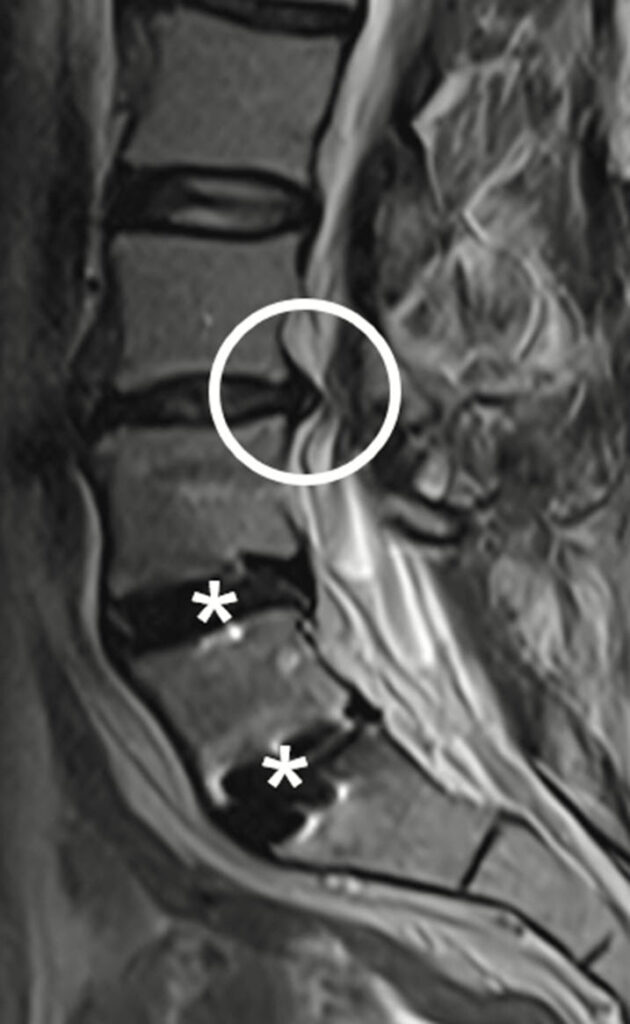

MRT (Magnetresonanztomographie)

→ Abbildung Wirbelsäule und des Iliosakralgelenks – nach Spondylodese